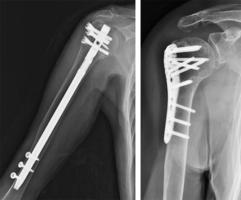

骨折の手術方法は、大きく分けて2種類あります。一つは髄内釘(ずいないてい)と呼ばれる方法であり、もう一つはプレート固定です。厳密にはもう一つ、創外固定という方法がありますが、今回は割愛します。

髄内釘は、骨折した部位と離れたところから骨の中の部分に芯棒を入れ、折れたところを固定する方法です=図1=。芯棒を入れただけでは折れた骨が回旋する心配があるので、芯棒の両端に開けられた穴にスクリュー(ネジ)を入れることもあります。この方法は骨折したところを開かないため、骨折の治癒に必要とされる骨膜(骨の表面を被(おお)う膜)が温存されるという利点がありますが、骨の端の部分の骨折には、適応しづらいという欠点があります。

一方、プレート固定は骨折した部位を開き、折れた骨同士をきちんと合わせた後に金属製のプレート(板)を当て、スクリューで固定する方法です=図2=。この方法は、骨のどの部位の骨折でも適応できるという利点がありますが、折れた骨同士をきちんと合わせるために、いったん骨膜を骨から?がす操作が必要となり、その分治癒に時間がかかることがあります。二つの図は、上腕骨の骨折における髄内釘とプレート固定の、それぞれのX線写真を示しています。